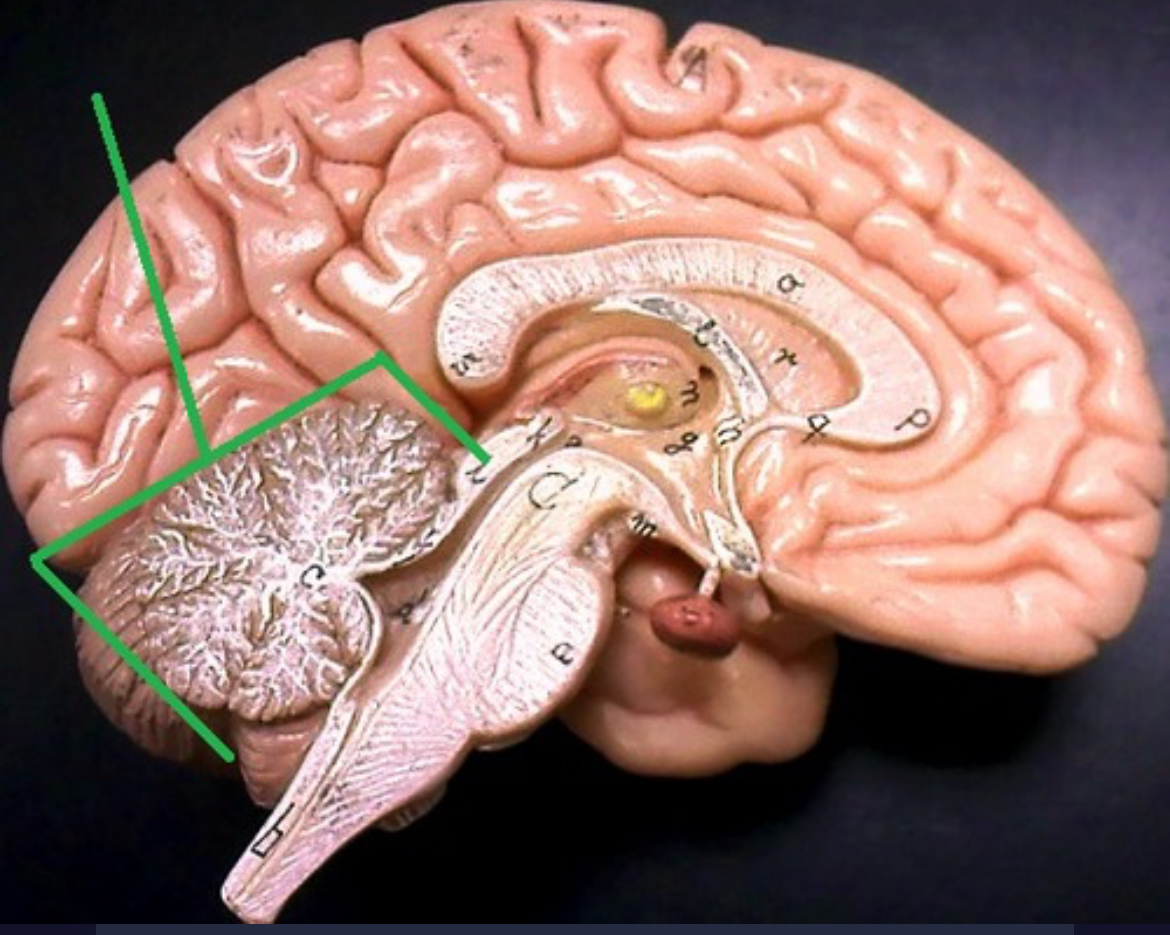

Central sulcus

Cerebellum

Corpus callosum

Diencephalon

Thalamus

3rd ventricle

Hypothalamus

Epithalamus (pink line)

Brain stem

Pons

Medulla oblongata

Choroid plexus of 3rd ventricle

Cerebral aqueduct (midrain)

4th ventricle

central canal